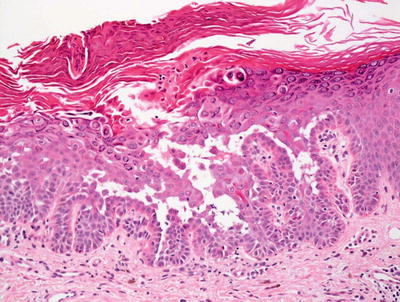

3.3.2 Histology

Histologic changes consist of a non-inflammatory subcorneal blister at the level of the granular layer (Fig. 3.7). In many cases, the stratum corneum, which is the blister roof, is desquamated and not present in the biopsy specimen. Its absence is often overlooked, making the diagnosis difficult. Rare acantholytic cells may be observed within the granular layer (Fig. 3.8). There is virtually no underlying inflammation within the dermis. Special stains for bacteria are negative [15].

Fig. 3.7

Staphylococcal scalded skin syndrome features a subcorneal blister in the absence of any inflammatory infiltrate